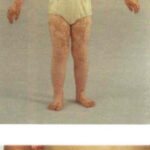

Patients with vitiligo present with one to several amelanotic macules that appear chalk- or milk-white in color. The lesions are usually well-demarcated, but the margins may be scalloped. They are accentuated on Wood's lamp examination. Lesions enlarge centrifugally at an unpredictable rate and can appear on any body site, including mucous membranes. However, initial lesions occur most frequently on the hands, forearms, feet, and face. When vitiligo occurs on the face, it often favors a perioral and periocular distribution.

Vitiligo is classified as segmental, acrofacial, generalized, and universal, or by pattern of involvement as focal, mixed, and mucosal types.

Depending on ethnic color, vitiligo is more or less conspicuous .

Trichrome vitiligo is characterized by both depigmented and hypopigmented macules in addition to normally pigmented skin. The natural evolution of the hypopigmented areas is progression to full depigmentation. Quadrichrome vitiligo refers to the additional presence of marginal or perifollicular hyperpigmentation. This variant is recognized more frequently in darker skin types, particularly in areas of repigmentation. Cases of pentachrome vitiligo have also been reported with additionally blue-gray hyperpigmented macules, representing areas of melanin incontinence (dermal melanin). Occasionally, patients with vitiligo may present with an unusual variant called the confetti type or vitiligo ponctue. These patients have several tiny, discrete hypomelanotic macules. Inflammatory vitiligo is characterized clinically by erythema at the margins of vitiligo macules.